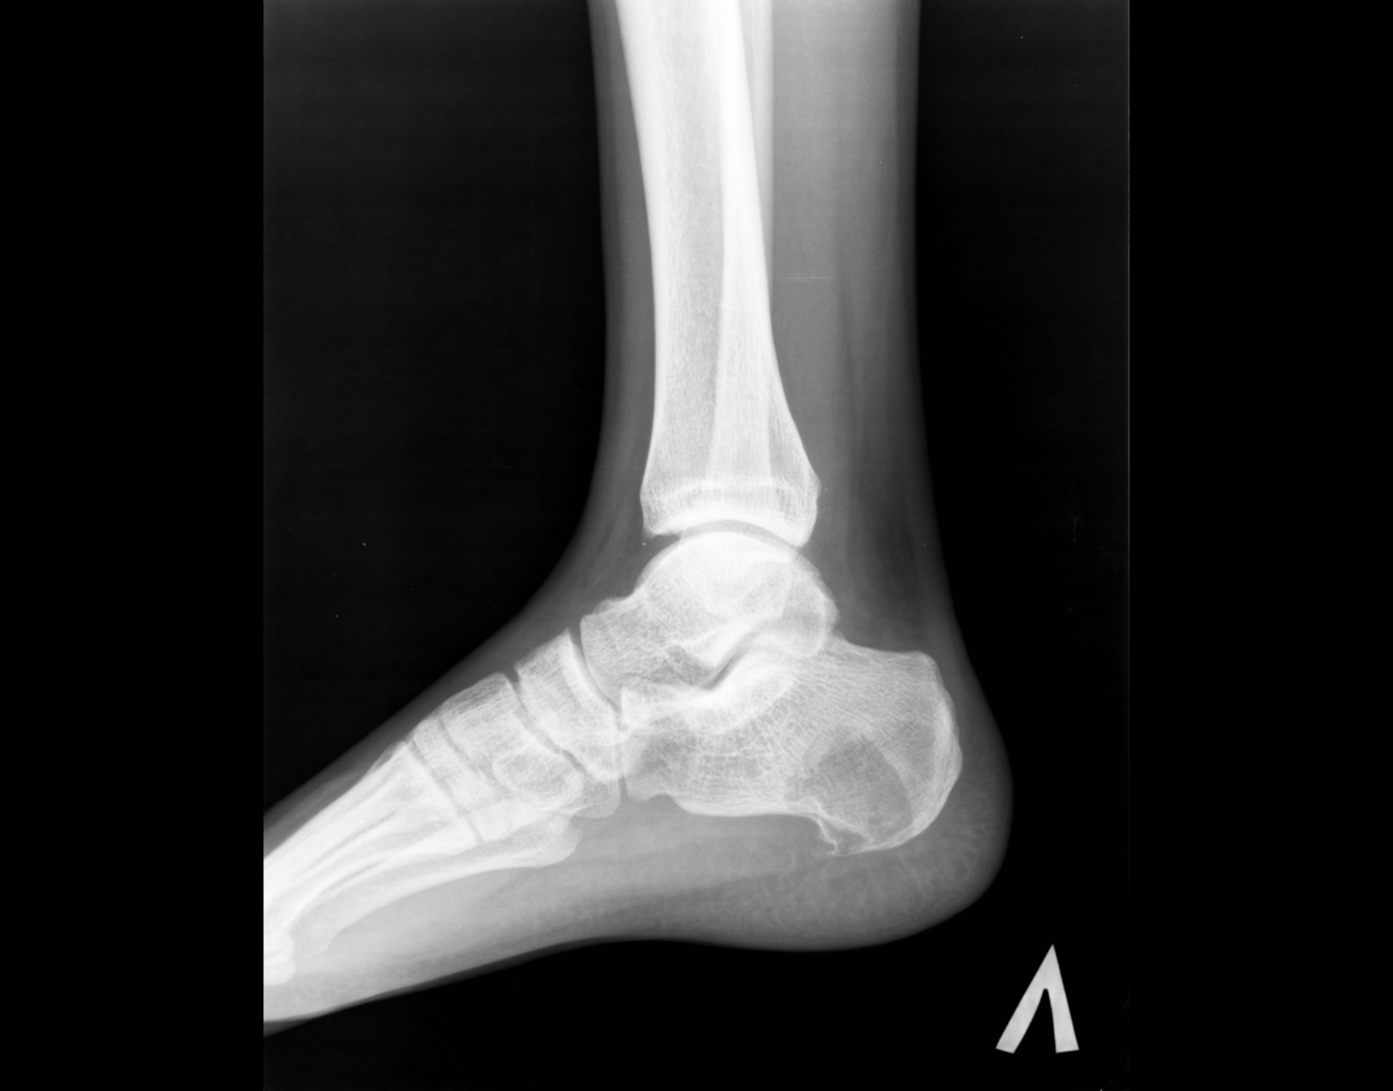

Здравствуйте! Я - молодой доктор, оставшийся один в отделении на целый месяц. Непонятных мне снимков много, вот отдин из них. Женщина 1938г.р., направлена на снимки голеностопного сустава с диагнозом: Артроз. Артроза не вижу, но пяточная кость вызывает подозрения. Что это может быть? Помогите разобраться.

Киста пяточной кости.

+1. Для опыта по-рекомендовал бы сделать аксиальный снимок и томограммы.

На самом деле, я бы в заключение вынесла "кисту" и рекомендовала МРТ